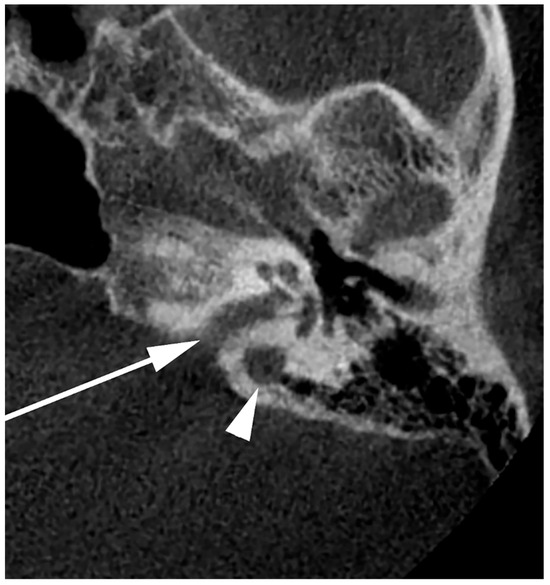

- Raghuram, K.; Cure, J.K.; Harnsberger, H.R. Condylar jugular diverticulum. J. Comput. Assist. Tomogr. 2009, 33, 309–311. [Google Scholar] [CrossRef]

- Jagtap, R.; Wazzan, T.; Hansen, M.; Kashtwari, D. Condylar jugular diverticulum: A report of 3 cases. Imaging Sci. Dent. 2019, 49, 251–256. [Google Scholar] [CrossRef]

- Parillo, M.; Vaccarino, F.; Mallio, C.A.; Quattrocchi, C.C. Right Condylar Jugular Diverticulum: Contrast-enhanced Computed Tomography Findings of a Rare Anatomical Variant of Jugular Bulb. Indian J. Otolaryngol. Head Neck Surg. 2023, 75, 2257–2259. [Google Scholar] [CrossRef] [PubMed]